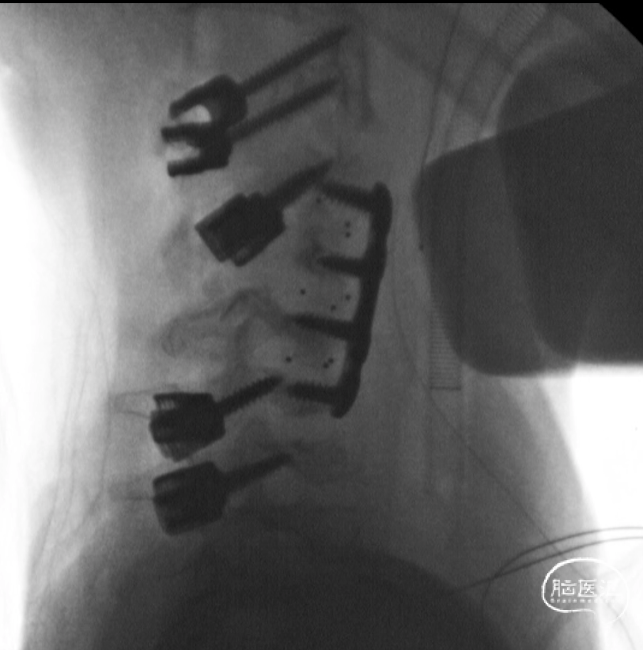

前路手术完成后,翻身行后路C2-C7置钉

C4及C5侧块无法置钉,双侧C5放置椎板钩增加把持力